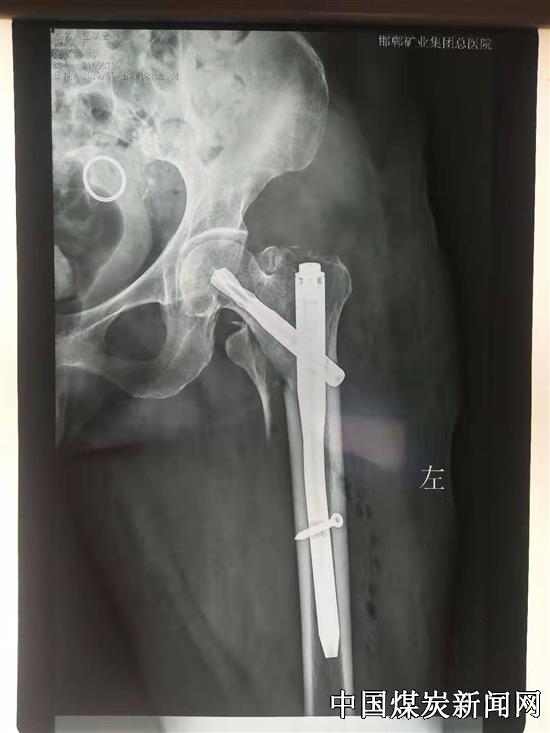

【本网讯】近日,患者刘奶奶的家属怀着感激的心情给华北医疗邯矿总医院骨外科送来了一面锦旗,感谢骨外科医生张志刚为74岁高龄的刘奶奶成功实施了左股骨粗隆间骨折闭合复位PFNA内固定手术治疗。

据了解,刘奶奶家住邯矿总医院附近,因不慎摔伤,致左股骨粗隆间骨折,就诊于邯矿总医院。入院后,骨外科医疗团队在陈志东主任的带领下,积极完善相关检查,严谨设计手术方案。入院第二天即行左股骨粗隆间骨折闭合复位PFNA内固定手术治疗。刘奶奶术后恢复良好,术后3天下地行走,未出现肺炎、褥疮、深静脉血栓等并发症,顺利出院,刘奶奶和家人逢人就夸邯矿总医院骨外科技术好、服务好,还有专业的医疗团队,对骨外科的医护人员是暂不绝口。

邯矿总医院外科医疗团队在陈志东主任带领下积极开展相关研究,对股骨粗隆间骨折采取闭合复位PFNA内固定术,手术时间一般在30分钟左右,创伤小,降低了手术风险。为广大老年患者带来福音。